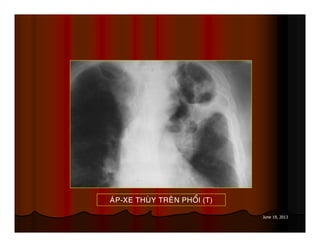

AÙP-XE THUØY TREÂN PHOÅI (T)

June 19, 2013 AÙP-XETHUØY TREÂN PHOÅI (T)